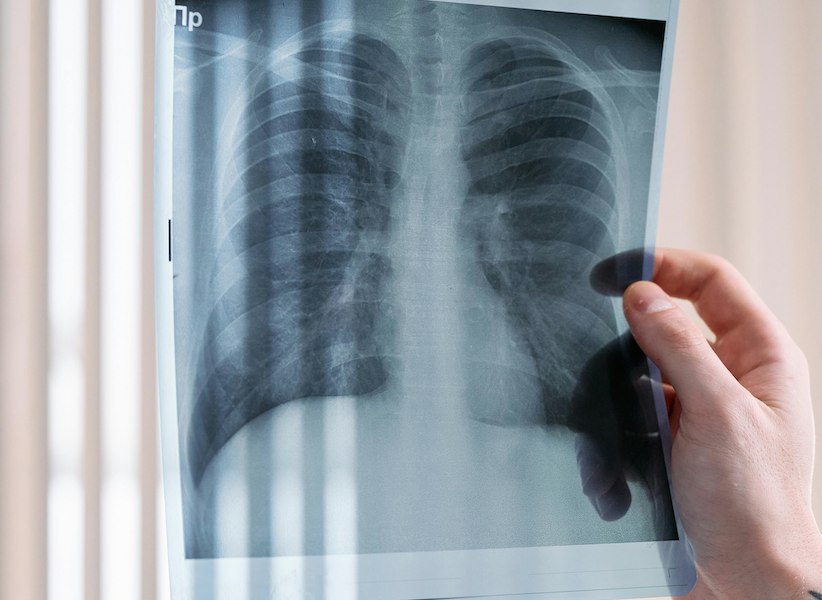

Luchtlekkage van de longen komt vaak voor na een longoperatie. Bob Hermans van het Radboudumc promoveert op onderzoek naar een nieuwe weefselpleister, die goede resultaten laat zien in een diermodel.

Jaarlijks krijgen wereldwijd meer dan twee miljoen mensen longkanker. Naar schatting wordt een kwart van hen geopereerd en kampen daarna ongeveer 50.000 mensen met een zogenoemde langdurige luchtlekkage. “Na zo’n longoperatie ontsnapt bij veel patiënten nog wel wat lucht vanuit de long”, zegt Bob Hermans, arts-assistent op de afdeling hartlong chirurgie aan het Radboudumc. “In veel gevallen is dat na enkele dagen over, maar als dat langer duurt en niet vanzelf dichtgaat spreken we van langdurige luchtlekkage. Dit leidt tot een langere ligduur, meer complicaties en sterfte en hogere kosten.”

Een wond aan de longen – na een operatie of ongeluk – kan bijvoorbeeld worden gehecht, dicht geniet of gelijmd met een spray of pleister. De keuze is vaak afhankelijk van de aard van de wond. Hermans: “Longweefsel is erg teer en hechtingen zijn eigenlijk alleen in het wat stevigere omhullende longvlies aan te brengen, met een kans op scheuren. Ook de andere technieken hebben hun eigen nadelen. Zo laten pleisters vaak weer los bij de normale longbewegingen na de operatie. We hebben onderzocht hoe een nieuwe pleister, een patch, het in dat opzicht doet. We hebben gekeken of hij goed blijft plakken, de wond effectief afdicht, veilig te gebruiken en biologisch afbreekbaar is.”

De pleister is een bestaand product, ontwikkeld door het Nijmeegse bedrijf GATT Technologies en eind 2023 op de markt gebracht door het bedrijf Ethicon. Overigens niet als een pleister om luchtlekkage te dichten maar als een dun sponsje om snel en effectief bloedingen te stelpen (hemostaticum). Hermans: “We hebben hetzelfde materiaal dus getest voor een nieuwe toepassing, namelijk het dichten van luchtlekkages. In ons onderzoek vooralsnog in een diermodel en de eerste resultaten zijn positief. De pleister heeft een grote plakkracht en blijft in vergelijking met andere pleisters goed zitten. Het materiaal veroorzaakt ook geen extra ontstekingsreacties, laat normale wondgenezing toe en lijkt na zes weken helemaal opgelost.”

Die eerste resultaten maken de patch interessant voor verder onderzoek. Belangrijke zaken die volgens Hermans nog goed bekeken moeten worden zijn de effectiviteit en veiligheid op lange(re) termijn. “Met name bij patiënten bij wie de longen minder goed functioneren door bijvoorbeeld COPD of een andere longaandoening. Luchtlekkage van de longen zien we vooral in deze patiëntengroep, terwijl ik mijn onderzoek uitsluitend heb uitgevoerd op gezond longweefsel.”